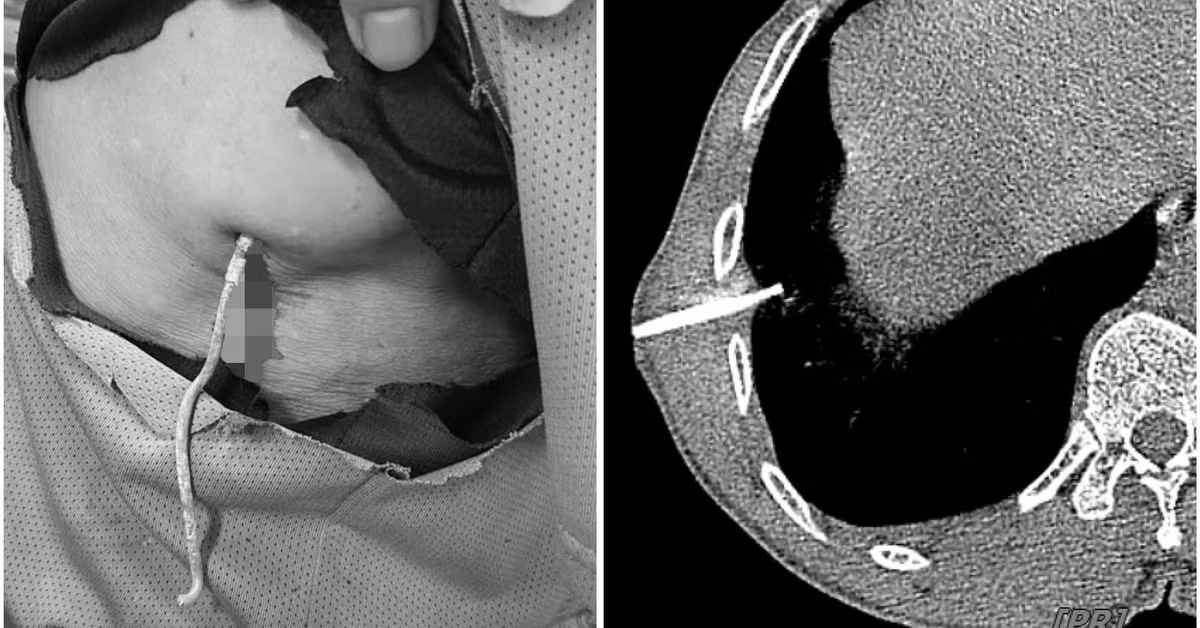

Ngày 8/4, thông tin từ Bệnh viện Hữu nghị Việt Nam - Cuba Đồng Hới (Quảng Bình) cho biết vừa cứu sống một nam sinh bị thủng thận.

Trước đó, em H.G.B (học sinh một trường THCS trên địa bàn TP.Đồng Hới) nhập viện trong tình trạng mệt mỏi, đau ngực, buồn nôn, đau bụng hạ sườn trái.